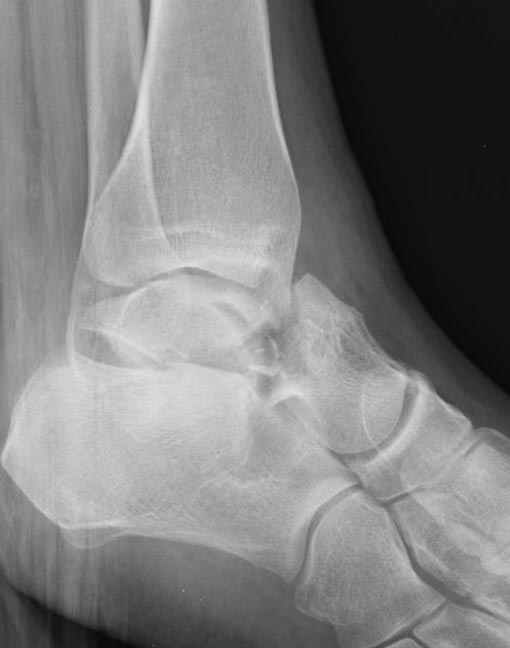

Вдогонку по поводу перелома таранной кости, больная 81, не страдает диабетом, перелом закрытый, в первый же день поступления ограничились временным наружным фиксатором (как на снимке).

Планировалась открытая фиксация после спадения отека, но больная пожелала лечиться по месту жительству в другом штате..

Из-за отека на стопе тактика лечения у всех была

одинаковая: временная наружная фиксация до спадения отека, при изолированных переломах они выписывались домой и через дней 7 госпитализировались на оперативное лечение.

Примеры на снимке...